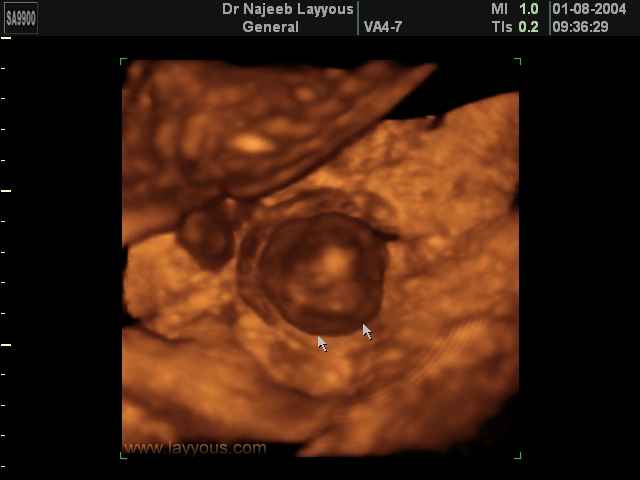

صور طبية للحمل بجهاز الالتراساوند | الدكتور نجيب ليوس